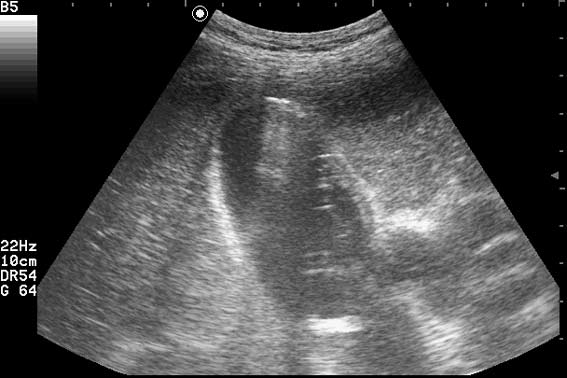

УЗИ Острый эмфизематозный холецистит. Эмпиема.

Пациент поступил в хирургическое отделение с жалобами на боли в правом подреберье и эпигастрии, повышение температуры. Болен 4 дня.

Острый эмфизематозный холецистит. Эмпиема ЖП. Паравезикул. абсцесс??? :roll: